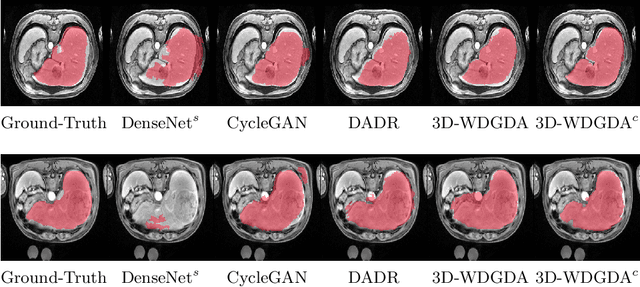

Abstract:Deep neural networks have shown exceptional learning capability and generalizability in the source domain when massive labeled data is provided. However, the well-trained models often fail in the target domain due to the domain shift. Unsupervised domain adaptation aims to improve network performance when applying robust models trained on medical images from source domains to a new target domain. In this work, we present an approach based on the Wasserstein distance guided disentangled representation to achieve 3D multi-domain liver segmentation. Concretely, we embed images onto a shared content space capturing shared feature-level information across domains and domain-specific appearance spaces. The existing mutual information-based representation learning approaches often fail to capture complete representations in multi-domain medical imaging tasks. To mitigate these issues, we utilize Wasserstein distance to learn more complete representation, and introduces a content discriminator to further facilitate the representation disentanglement. Experiments demonstrate that our method outperforms the state-of-the-art on the multi-modality liver segmentation task.

Abstract:A deep learning model trained on some labeled data from a certain source domain generally performs poorly on data from different target domains due to domain shifts. Unsupervised domain adaptation methods address this problem by alleviating the domain shift between the labeled source data and the unlabeled target data. In this work, we achieve cross-modality domain adaptation, i.e. between CT and MRI images, via disentangled representations. Compared to learning a one-to-one mapping as the state-of-art CycleGAN, our model recovers a many-to-many mapping between domains to capture the complex cross-domain relations. It preserves semantic feature-level information by finding a shared content space instead of a direct pixelwise style transfer. Domain adaptation is achieved in two steps. First, images from each domain are embedded into two spaces, a shared domain-invariant content space and a domain-specific style space. Next, the representation in the content space is extracted to perform a task. We validated our method on a cross-modality liver segmentation task, to train a liver segmentation model on CT images that also performs well on MRI. Our method achieved Dice Similarity Coefficient (DSC) of 0.81, outperforming a CycleGAN-based method of 0.72. Moreover, our model achieved good generalization to joint-domain learning, in which unpaired data from different modalities are jointly learned to improve the segmentation performance on each individual modality. Lastly, under a multi-modal target domain with significant diversity, our approach exhibited the potential for diverse image generation and remained effective with DSC of 0.74 on multi-phasic MRI while the CycleGAN-based method performed poorly with a DSC of only 0.52.

Abstract:Domain Adaptation (DA) has the potential to greatly help the generalization of deep learning models. However, the current literature usually assumes to transfer the knowledge from the source domain to a specific known target domain. Domain Agnostic Learning (DAL) proposes a new task of transferring knowledge from the source domain to data from multiple heterogeneous target domains. In this work, we propose the Domain-Agnostic Learning framework with Anatomy-Consistent Embedding (DALACE) that works on both domain-transfer and task-transfer to learn a disentangled representation, aiming to not only be invariant to different modalities but also preserve anatomical structures for the DA and DAL tasks in cross-modality liver segmentation. We validated and compared our model with state-of-the-art methods, including CycleGAN, Task Driven Generative Adversarial Network (TD-GAN), and Domain Adaptation via Disentangled Representations (DADR). For the DA task, our DALACE model outperformed CycleGAN, TD-GAN ,and DADR with DSC of 0.847 compared to 0.721, 0.793 and 0.806. For the DAL task, our model improved the performance with DSC of 0.794 from 0.522, 0.719 and 0.742 by CycleGAN, TD-GAN, and DADR. Further, we visualized the success of disentanglement, which added human interpretability of the learned meaningful representations. Through ablation analysis, we specifically showed the concrete benefits of disentanglement for downstream tasks and the role of supervision for better disentangled representation with segmentation consistency to be invariant to domains with the proposed Domain-Agnostic Module (DAM) and to preserve anatomical information with the proposed Anatomy-Preserving Module (APM).